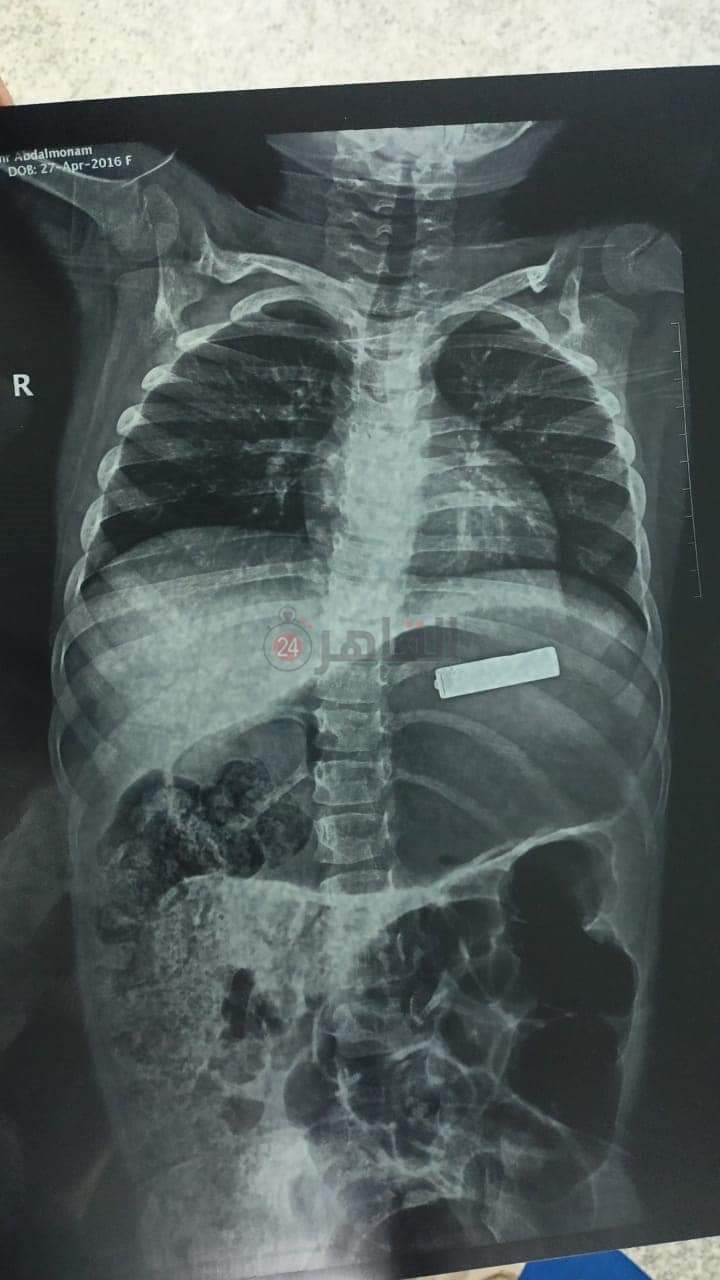

كشف الدكتور محمد أشرف عوض، الطبيب ونائب الجراحة بمستشفى أبو الريش بـ جامعة القاهرة، تفاصيل استخراج بطارية من طفلة عمرها 5 سنوات، مشيرًا إلى أن الطفلة وصلت لاستقبال أبوالريش منذ عدة الساعة 5 فجرًا ذلك بسبب بلع جسم غريب.

وأشار الدكتور محمد أشرف عوض الطبيب ونائب الجراحة بمستشفى أبو الريش بجامعة القاهرة في تصريحات خاصة لـ القاهرة 24، إلى أنه بعد سؤال الأهل تبين أن الجسم الغريب بطارية بها مواد كاوية حارقة، قائلًا: كان لا بد من التدخل السريع للحفاظ على سلامة الجهاز الهضمي من الحرق والانفجار.

وأوضح أشرف، أنه تم عمل منظار جراحي للمعدة واستخراج البطارية منها باستخدام ألة الـ dormia basket، مردفا: بعد ذلك تم حجز الطفلة في قسم الجراحة لحين تحسنها والاطمئنان علي شفاءها والتأكد من سلامة المرئ والمعدة.